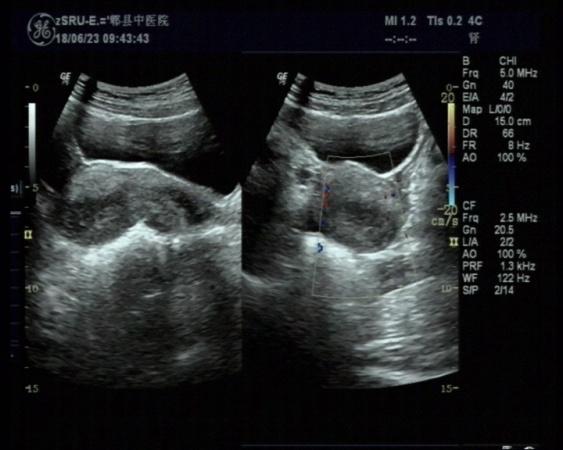

右侧附件区畸胎瘤可能

女,30岁,既往体检无异常,此次超声检查如图所示:右侧附件区探及一杂乱不均回声团,边界清楚,形态规则,CDFI:周边可见少许血流信号。